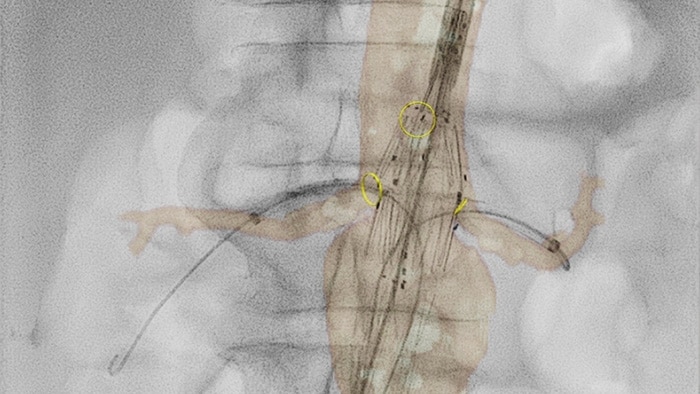

VesselNavigator fournit une feuille de route en 3D intuitive et continue basée sur des ensembles de données TDM et ARM existants pour vous guider à travers le système vasculaire pendant les procédures aortiques. Une étude a montré une réduction moyenne de 170 ml du contraste lors de la réparation endovasculaire des anévrismes aortiques complexes avec un guidage de fusion d’images TDM VesselNavigator.1 Une autre étude a montré une réduction de 6,3 à 5,2 (1,1) heures de la durée d’intervention moyenne lors de la réparation endovasculaire d’un anévrisme fémoral/à branches avec un guidage de fusion d’images TDM VesselNavigator.2

La solution Azurion de Philips a permis de percer dans l’amélioration des processus et ainsi d’obtenir des résultats prouvés en matière d’efficacité. Face au nombre croissant de patients atteints de maladies aortiques, Azurion offre un certain nombre d’innovations au niveau des processus de travail ayant pour but d’aider les équipes des services vasculaires à travailler de façon efficace et cohérente tout en restant focalisées exclusivement sur le patient et tout en gérant la dose de rayonnement pendant les interventions.